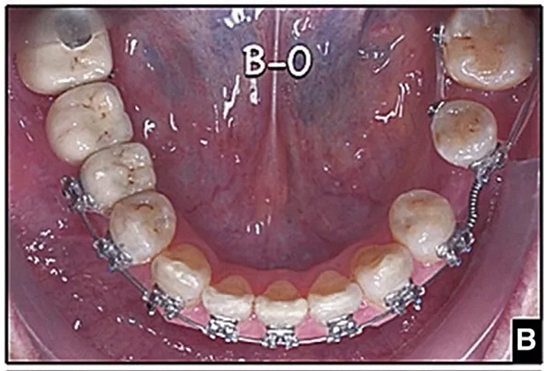

圖15.A,去除固定裝置一個月后,下頜左側(cè)第二前磨牙復(fù)發(fā),移動到種植體愈合的部位; B,B-0表示開始再治療,通過鏈圈和推簧的矯正復(fù)發(fā); C,B-9是治療結(jié)束后3個月回訪時下頜弓的咬合面觀,這是再治療階段的9個月。下頜左側(cè)第二前磨牙和第三磨牙的頰面粘合一個固定保持器,以防止復(fù)發(fā)。